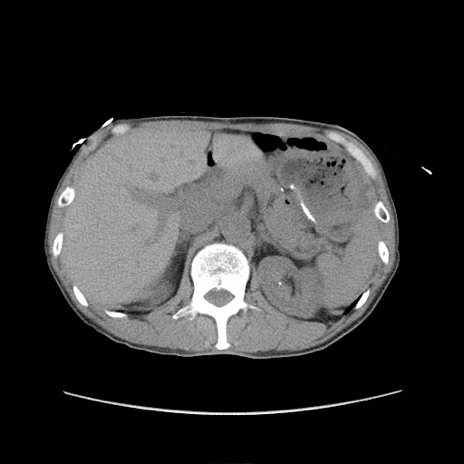

冠状断像

症例11(横断像)

【症例】 60歳代男性

【主訴】 下腹部痛

【現病歴】 本日夜中より下腹部痛の症状認め、受診。

【既往歴】 膀胱癌(膀胱全摘+尿管皮膚瘻術) 、胃癌術後

【身体所見】 BT 35.3℃、PR 58/min、BP 136/98mHg、腹部平坦、軟、腸蠕動音±、ストマ留置あり、左上腹部~正中部に圧痛あり、反跳痛なし。

【データ】WBC 5100、CRP0.01